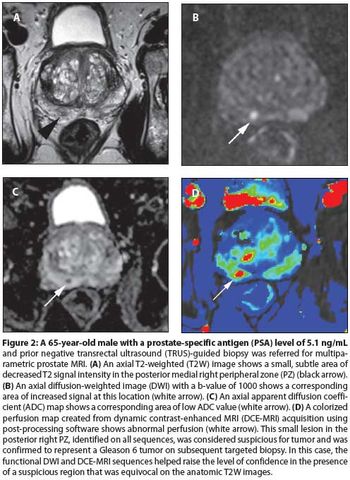

ByRajan T. Gupta, MD,Christopher R. Kauffman, MD,Thomas J. Polascik, MD, FACS,Samir S. Taneja, MD,Andrew B. Rosenkrantz, MD Our aims in this article are to describe the various imaging sequences that comprise the multiparametric MRI exam, as well as to review current literature on the strengths/weaknesses of these sequences; to delineate strategies for standardizing interpretation and reporting of MRI results; and to expound on the role of prostate MRI in clinical practice.